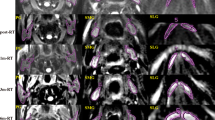

All subjects successfully underwent the whole therapy and follow-up MR examinations. No measurement was excluded because of insufficient quality. The pre- and post-RT DWI and ADC images of bilateral PGs and SMGs of one representative subject are shown in Fig. 1. Excellent reproducibility of the measurement of ADC for both PGs and SMGs was achieved, with the inter-observer ICC at 0.92 (P < 0.001) and the intra-observer ICC at 0.94 (P < 0.001). The main characteristics of subjects and tumor are presented in Table 1.

Diffusion weighted imaging (DWI) and apparent diffusion coefficient (ADC) images of bilateral parotid glands (PGs; white solid arrow) and submandibular glands (SMGs; white hollow arrow) of a 49-year-old male NPC patient at different timepoints pre and post RT. For both PGs and SMGs, ADC images illustrated a relatively slightly higher signal at 1m-post-RT and 3m-post-RT compared to that of pre-RT, with a gradually decreasing signal at 6m-post-RT and 12m-post-RT. Meanwhile, the metastatic lymph nodes (white arrow) apparently disappeared after 1m-post RT